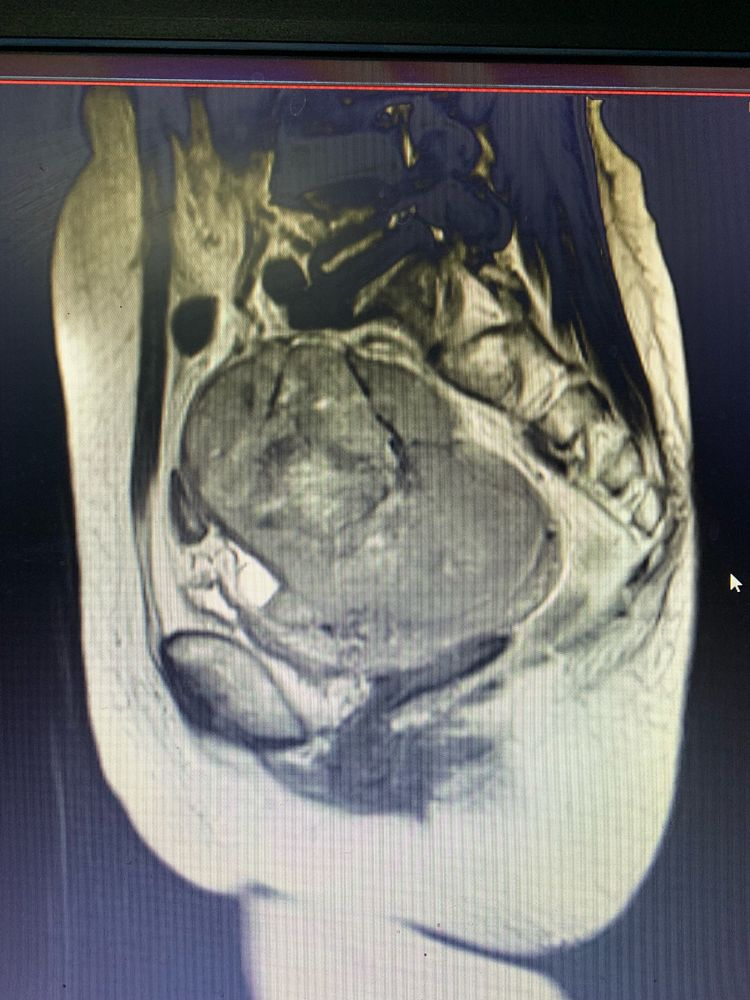

董徐男主任熱情接待并立即安排患者入院完善進(jìn)一步檢查。行VCT及MR檢查提示:盆腔巨大占位病變,考慮子宮或左附件來源的惡性腫瘤,腫塊前方侵犯乙狀結腸全層,患者手術指征明顯,由于手術範圍大、風險高,董徐男主任積極申請醫院多學(xué)科會(huì)診,通過(guò)邀請胃腸肝膽外科、病理科、放射科、功能(néng)科、消化内科、麻醉手術中心、眼科、腫瘤血液科、心血管内科/老年病科、營養科、泌尿外科、重症醫學(xué)科等多學(xué)科進(jìn)行會(huì)診,評估患者病情,做好(hǎo)術前準備。

入院初步考慮是子宮腫瘤,放射科吳慧忠主任、鄭業坤副主任醫師結合患者影像學(xué)情況,組織全科讨論研究,認爲可能(néng)是子宮意外來源的腫瘤侵入子宮内生長(cháng),并考慮有腸道(dào)轉移可能(néng);